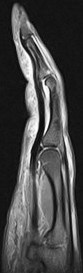

37 y/o male 4th finger injury with pain.

Annular pulley tears result in bowstringing of the tendon. Compare the sagittals of the 4th finger with the sagittal of the 5th finger which is not bowstrung (5th is labeled). I dont believe I have recognized only half of the pulley torn before.

Ulnar aspect A3 pulley tear with bowstringing of the flexor tendons